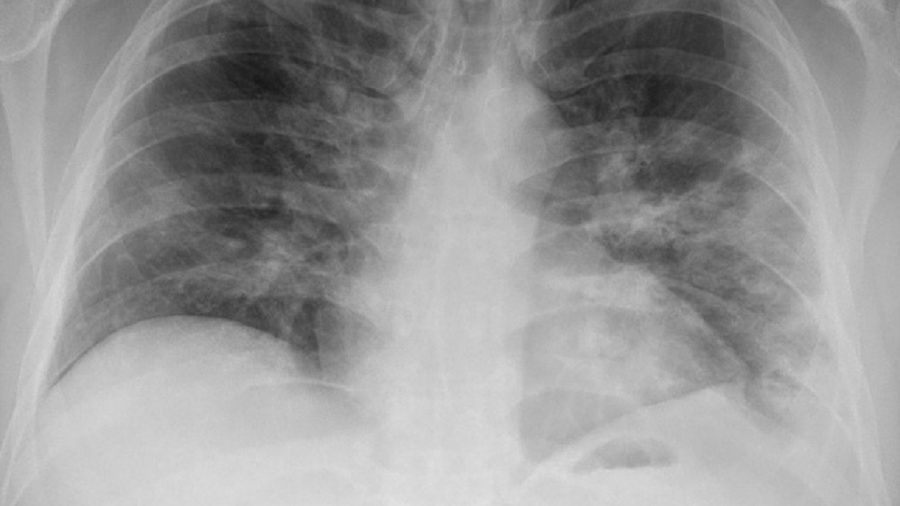

płucaPłuca pacjentów z koronawirusem mogą być całkowicie zniszczone.

Źródło zdjęć: © Getty Images

Naukowcy z King's College London przebadali płuca osób zmarłych na COVID-19. Odkryli nie tylko trwałe i rozległe uszkodzenia, ale także pewne unikalne cechy, które mogą wyjaśnić, co powoduje takie szkody w organizmie.

Zespół badaczy przeanalizował próbki z płuc, serca, wątroby i nerek 41 pacjentów zmarłych z powodu COVID-19. Ofiary COVID-19 pochodziły z włoskiego szpitala uniwersyteckiego w Trieście z okresu od lutego do kwietnia 2020 r. Badania opublikowano w czasopiśmie Lancet eBioMedicine.

W płucach znaleziono "naprawdę ogromne zniszczenie architektury płuc" i zdrową tkankę "prawie całkowicie zastąpioną bliznowatą tkanką". Według naukowców nawet jeśli ktoś pokona COVID-19, wyrządzone szkody mogą być ogromne i nieodwracalne. Ponadto w wielu tkankach wirus był nadal obecny.

U większości pacjentów wykryto kilka cech charakterystycznych tylko dla COVID-19. Była to m.in. rozległa krzepliwość krwi w tętnicach płucnych i żyłach. Ponadto niektóre komórki płuc wyjątkowo się powiększyły i miały wiele jąder - to wynik fuzji różnych komórek w pojedyncze duże komórki w procesie znanym jako syncytia.